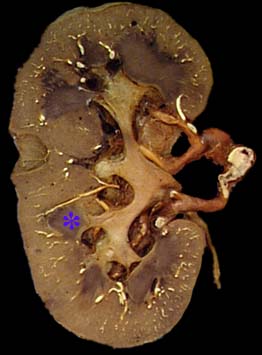

Kidney- cortex

Kidney- hilum

Kidney- sinus

Major calyx

Minor calyx

Renal capsule

Renal columns

Renal pelvis

Renal pyramid